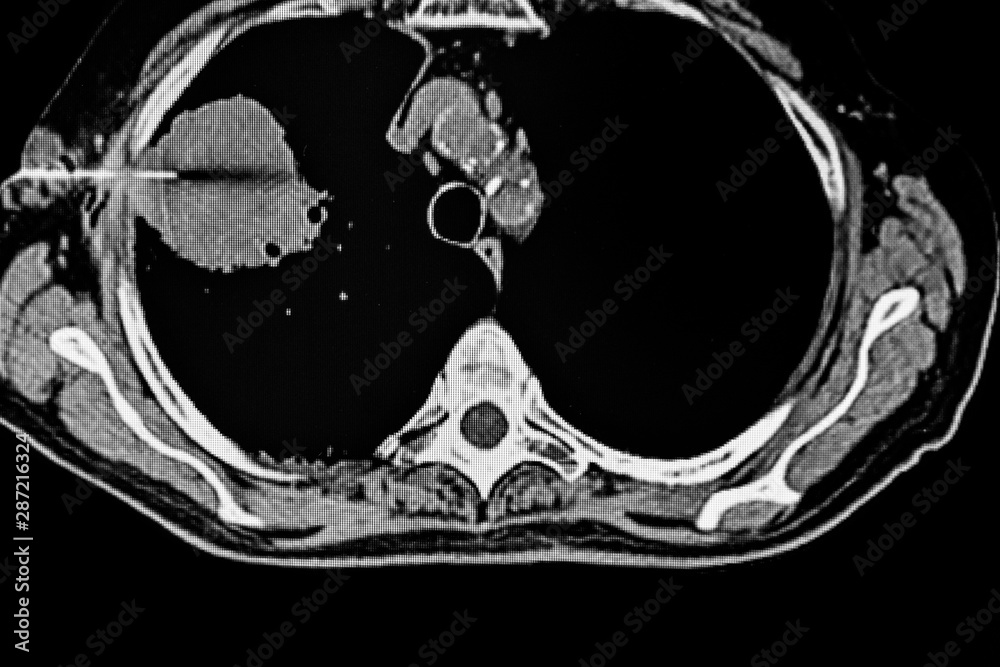

From stock.adobe.com

CAT Scan of Transthoracic fine needle aspiration in a patient with a Transthoracic Needle Aspiration Definition Transthoracic needle aspiration (ttna) has been used to diagnose disease in the lung for many decades. Transthoracic needle aspiration biopsy (tnab) is a useful diagnostic technique in the evaluation of thoracic disease. Percutaneous lung lesion biopsy (pllb) is a procedure that involves passing a needle percutaneously under image guidance. Transthoracic needle aspiration refers to percutaneous biopsy performed with a help. Transthoracic Needle Aspiration Definition.